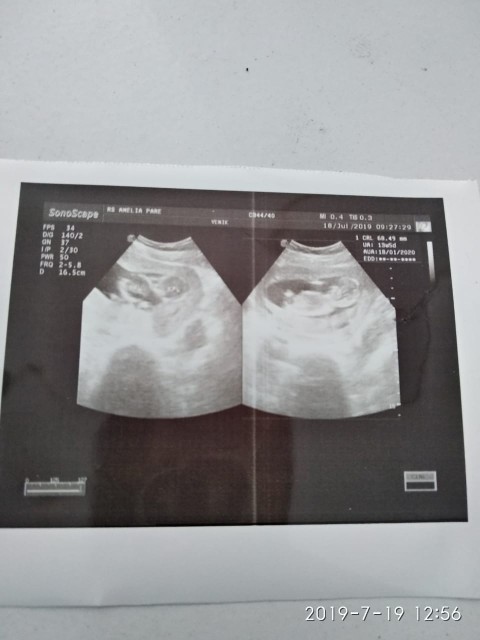

Bund, usia kandunganku 6 week, kemarin pas usg dokter bilang perkiraan punya calon ddek kembar.. Apa benar ya bund?? Kan usia kandungannya baru segitu kok udah bisa di prediksi gitu ya.. Sharing dong bund, ada yang pernah kayak gitu gak??

Kan keliatan kantung nya ada 2 bun

udh keliatan ada 2 kantong ny bund

Itu kantong janinnya ada 2 beb...

Kantung kehamilannya ada dua bun

Ada dua kantong bun emang kembar

Kantongnya 2 mom. Bisa jd kembar